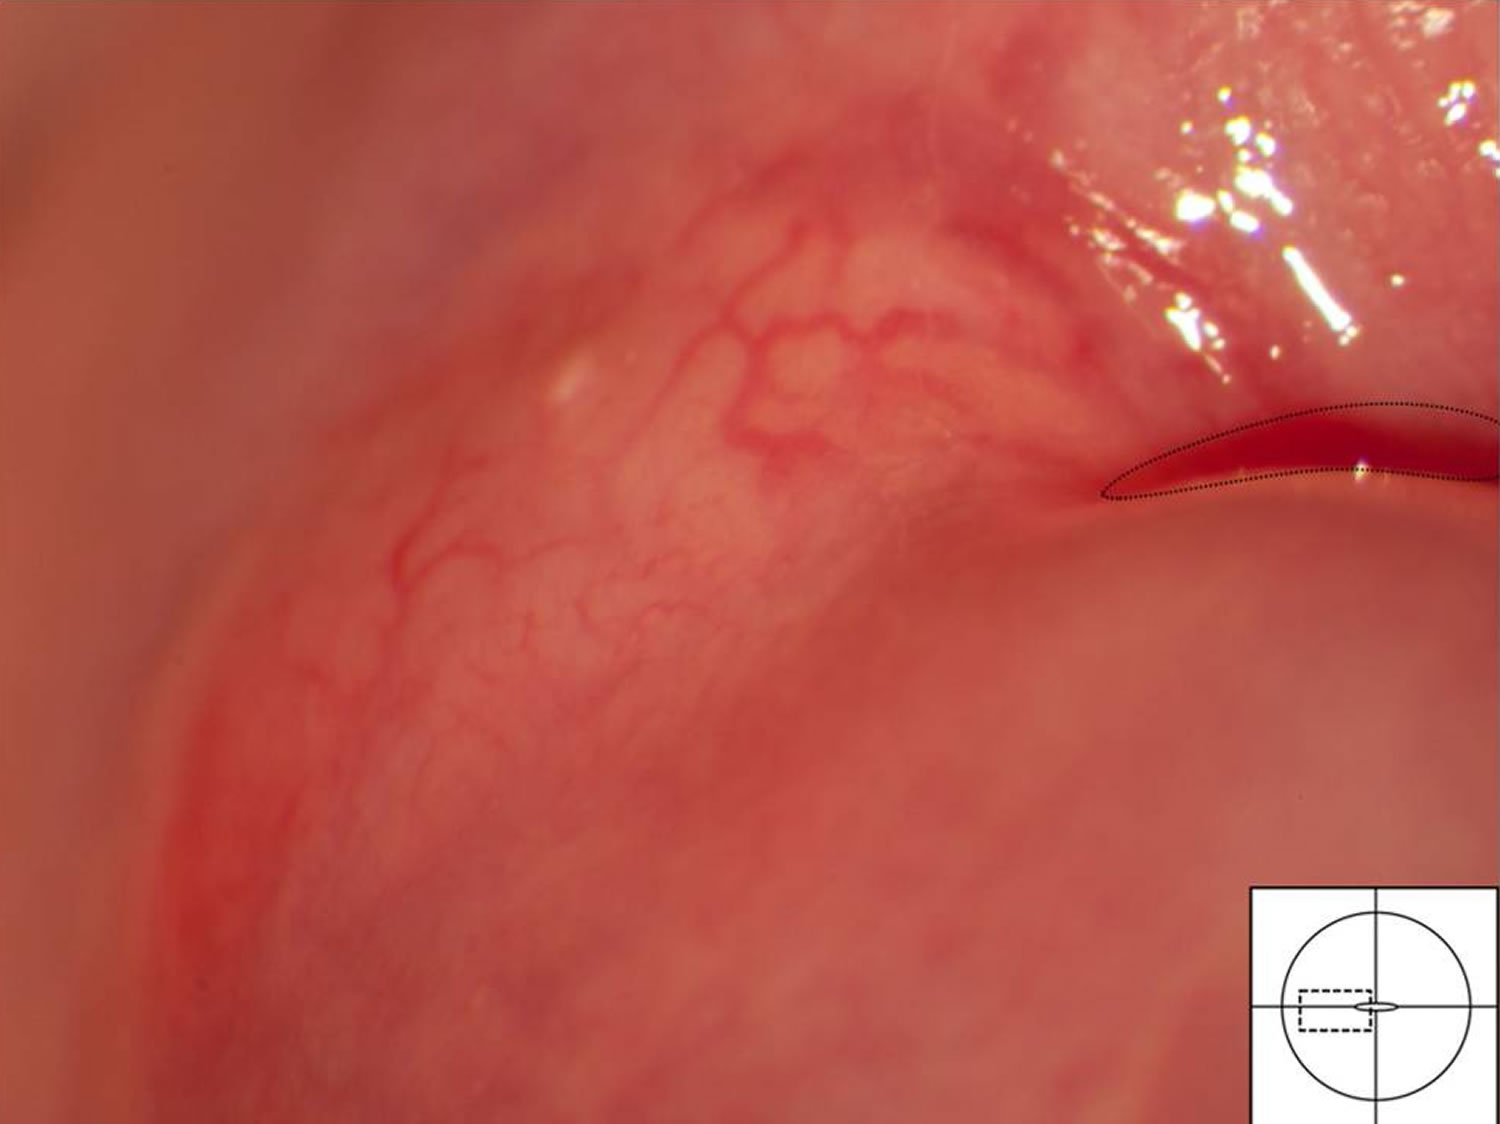

PPT Patología no Neoplásica del Cérvix PowerPoint Presentation ID2213666

Pathology Outlines Nabothian cysts